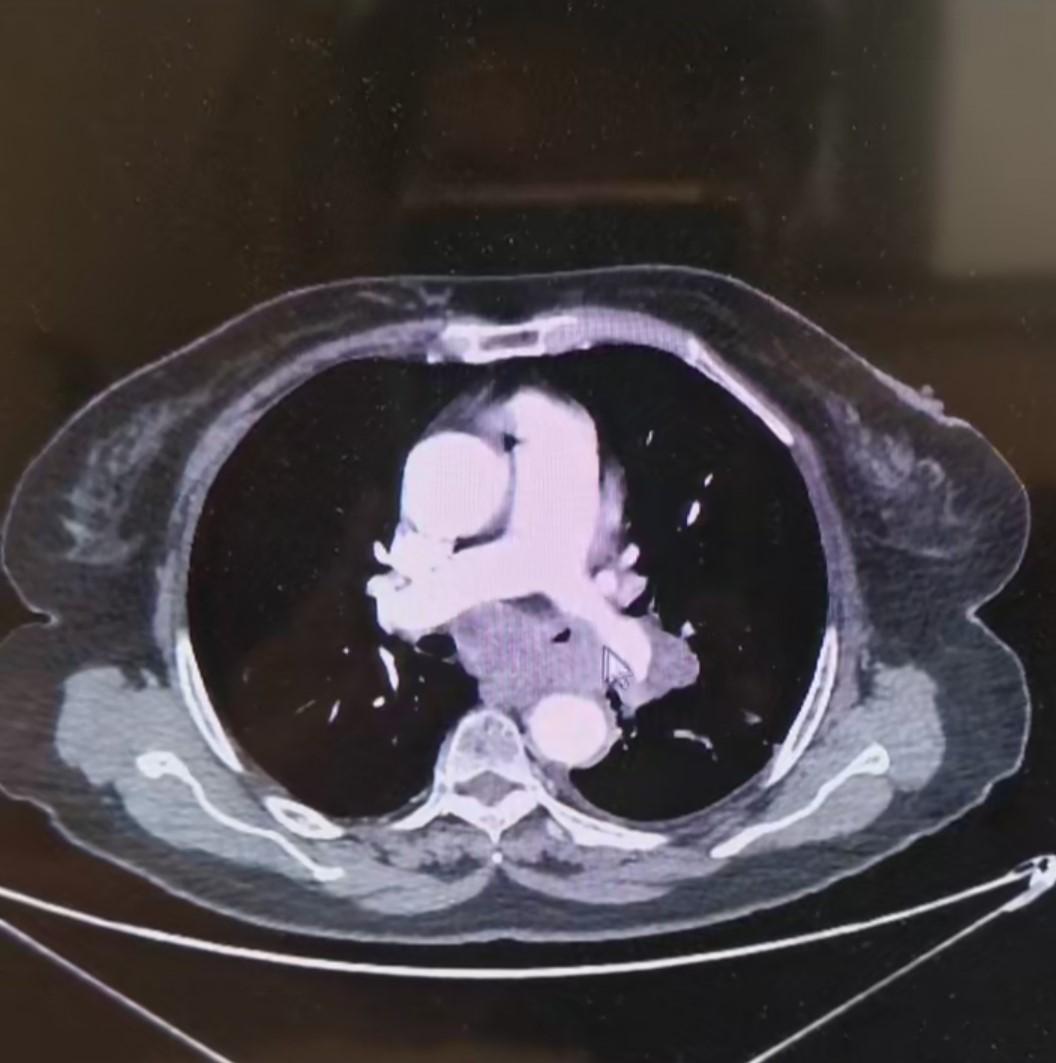

支气管动脉灌注治疗之前

经过手术后,患者情况得到好转,通过片子我们可以看到分叉的地方肿瘤都变得非常小,虽然没有治愈患者,但是我们用这些手段让病人的痛苦大大的减小生存期也得到了延长,这就是我们治疗的目的,看到患者情况好转,有了很大的恢复,患者儿子告诉我们,这已经超出了他们的预期,虽然没有彻底治愈他的父亲,但是让他们看到希望,给了他们在绝望中一缕曙光,也能够给他们一些陪伴父亲的时间。